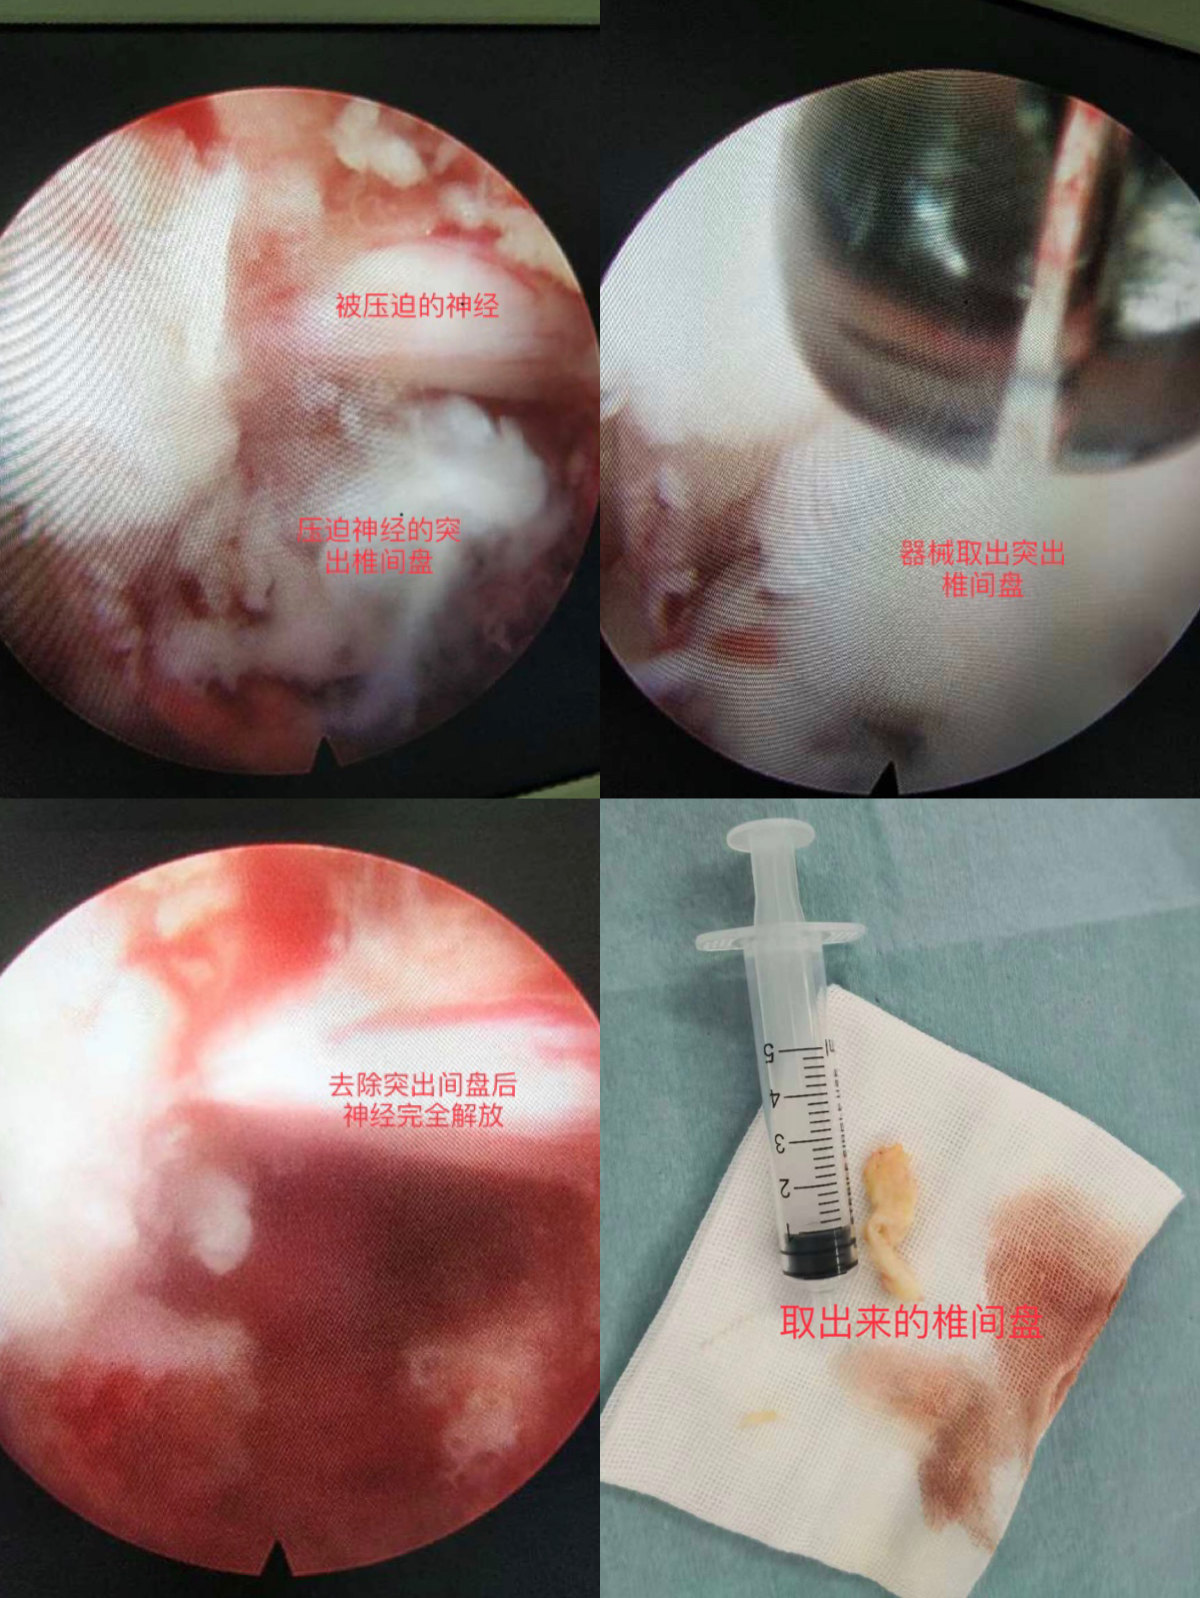

发现以及摘除突出椎间盘

通过屏幕观察找到压迫神经的突出椎间盘,然后用器械将突出间盘取出来,探查有无残留,止血结束手术。见下图。